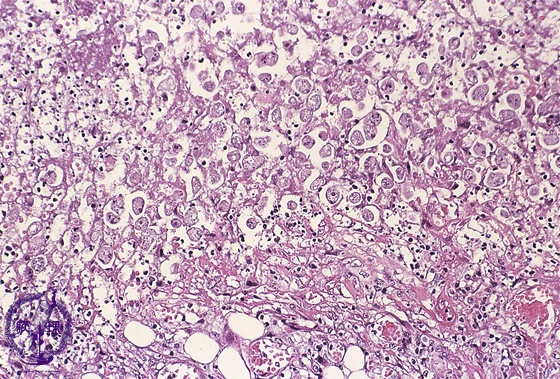

Microscopic view (H&E stain, high power): Many amoeba trophozoites are seen forming cysts.